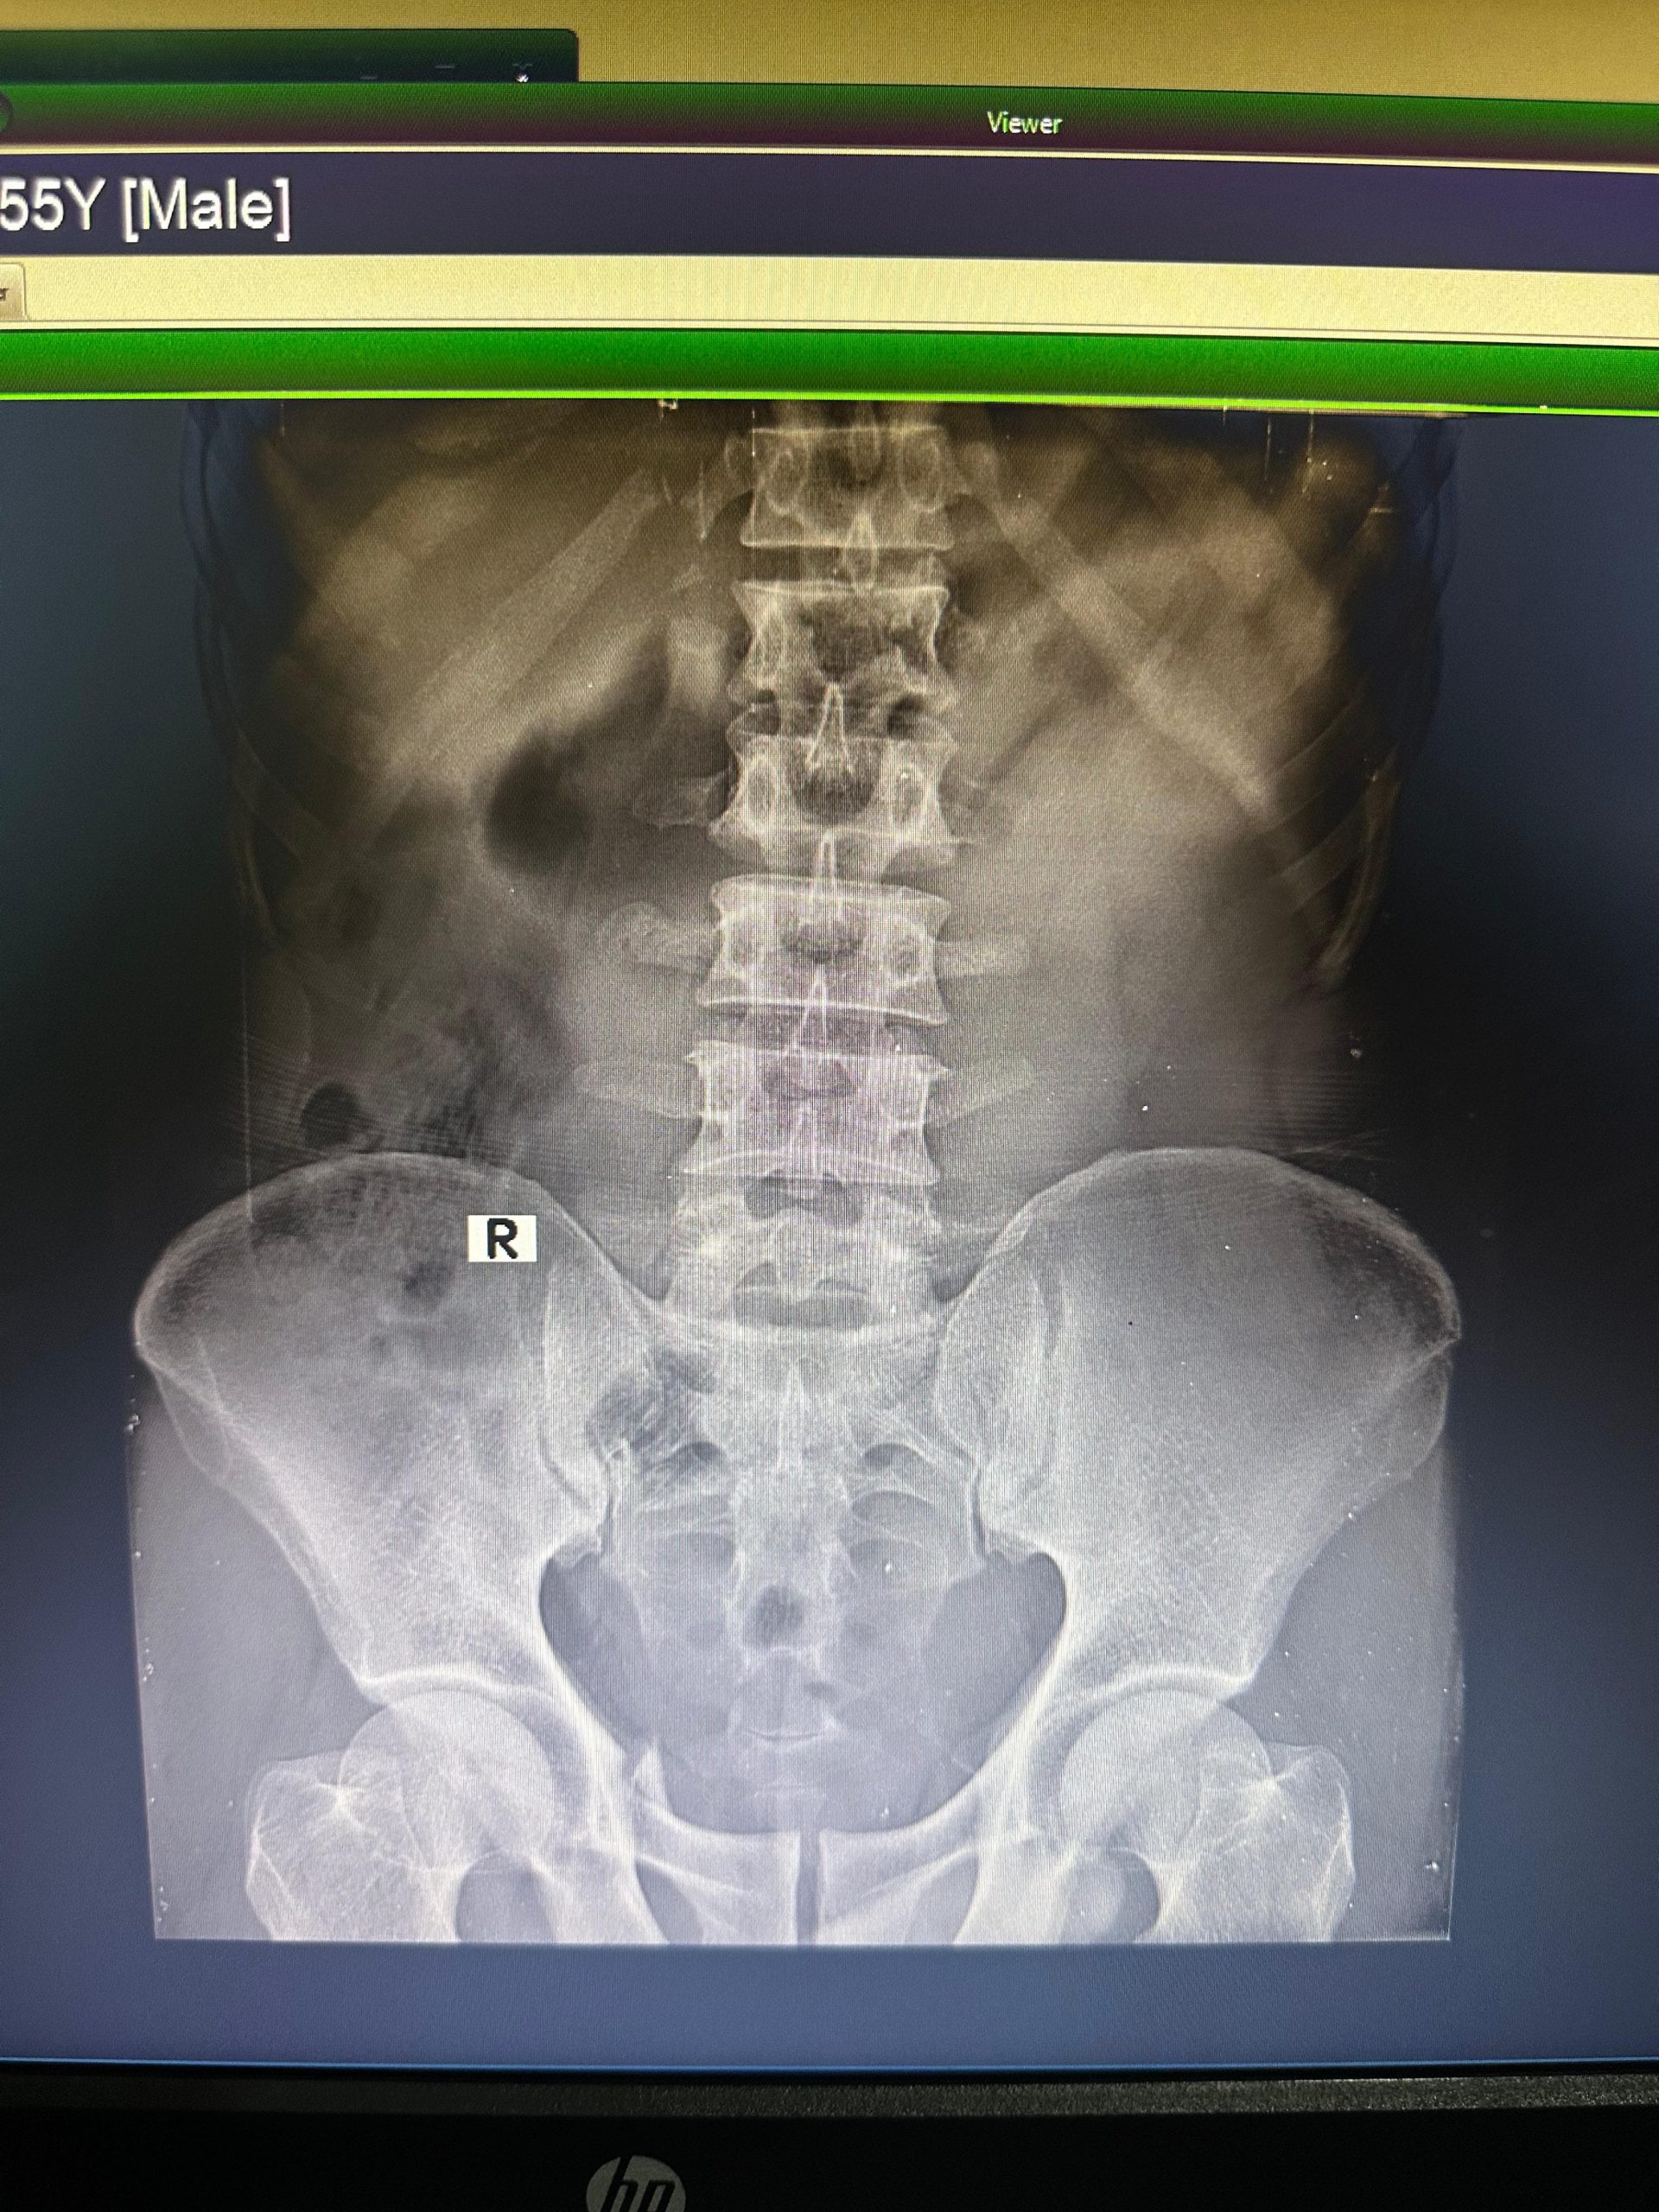

কুয়াকাটা ২০ শয্যা হাসপাতালের দায়িত্ব প্রাপ্ত উপসহকারী মেডিকেল অফিসার রিয়াজ উদ্দিন বলেন মোজাম্মেলের মেরুদন্ডে ফ্র্যাকচার হয়েছে পাজরে একটি হাড্ডি ভেঙ্গে গেছে তার অবস্থা গুরুতর হওয়ায় বরিশাল শেরে বাংলা মেডিকেল কলেজ হাসপাতালের অর্থোপেডিক্স বিভাগে প্রেরণ করা হয়েছে।